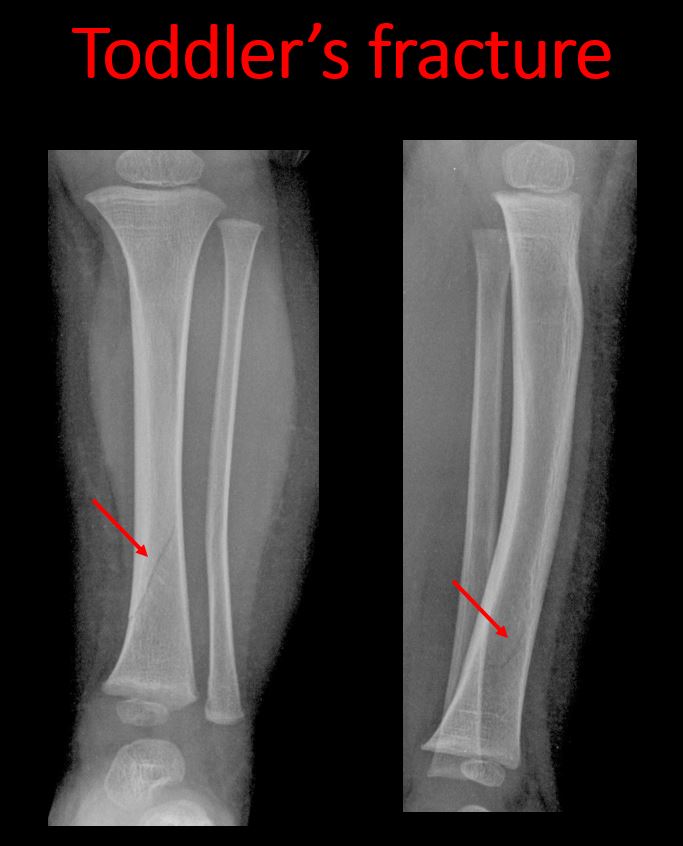

There is a break or interruption of the continuity of the cortical or cancellous bone with or without displacement of a fracture fragment which could be from a greenstick or toddler’s fracture, or other fracture. |

Yes | NA |